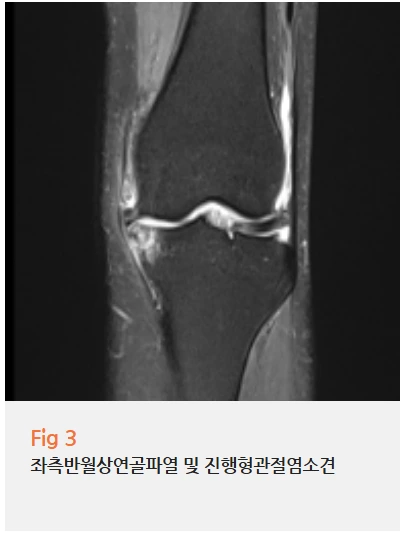

결과를 보는 순간 '역시나' 싶었습니다.

✅ 무릎 - 좌측 반월상연골 파열로 인한 무릎관절염

✅ 허리 - 요추 3-4, 4-5, 5번과 천추 1번 사이 협착증을 동반한 디스크 및 척추전방전위증

두 군데 모두 상당히 진행된 상태였어요.

이 환자분은 오래된 무릎 질환이 있었는데,

이를 제대로 관리하지 못하면서

허리까지 퇴행성 변화가 가속화된 케이스였습니다.